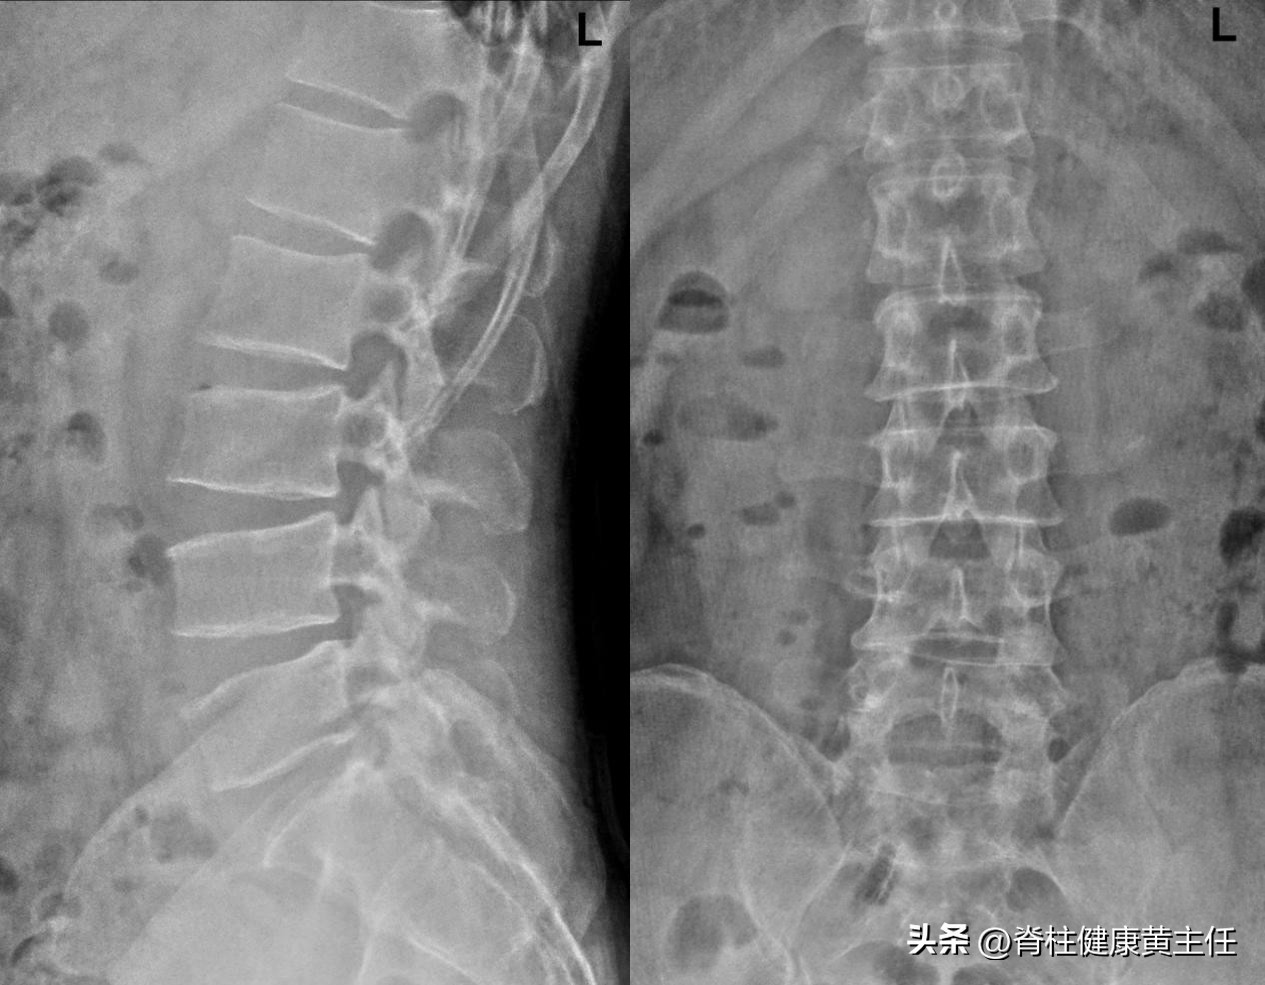

2、X光检查: 2023.8.14腰椎X光检查专科描述示,腰椎棘突排列连线不等直,腰椎生理曲度存在,椎体连续,骨质结构良好。